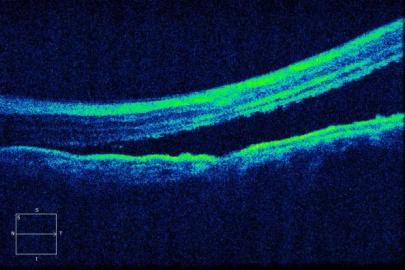

术前

左眼OCT提示黄斑区视网膜脱离